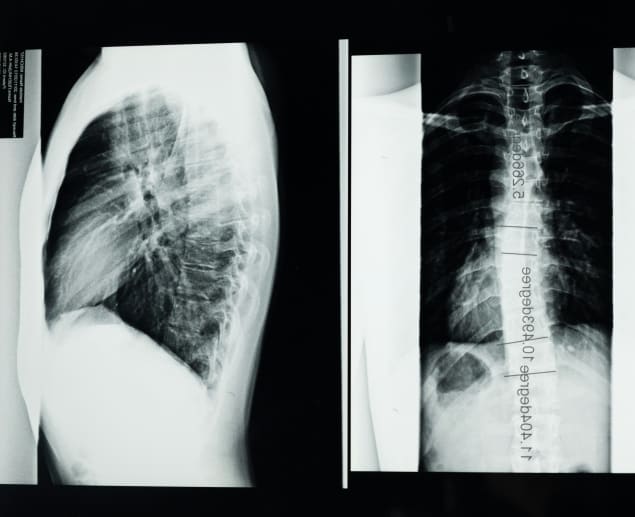

What does scoliosis look like on an X-ray?

On an X-ray image, scoliosis appears as an abnormal sideways curvature of the spine. Knowing how to read scoliosis images can help you understand what your clinician will explain after the scan.

Instead of the spine being straight when viewed from the back, there will be an S or C-shaped curve to the side. It may be less noticeable in mild scoliosis X-rays and more noticeable in severe scoliosis X-rays.

The scoliosis X-ray can also show if the condition is causing the spine to twist or rotate in addition to curving to the side. This rotation is commonly seen in severe scoliosis; the spine may look more like a ribbon.

A severe scoliosis X-ray may show a raised or protruding rib cage, and the vertebrae in the curved area of the spine may look abnormally wedge-shaped from the pressure and rotation of the spine in scoliosis pictures.